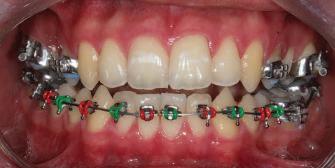

20 Dental Tribune Bulgarian Edition / октомври 2022 г. П ациентите със завършен растеж и скелетни проблеми обикновено представляват предизвикателство за ортодонт ската практика. Необходимостта от изваждане на зъби в комбинация с особеностите на възрастовата ортодонтия изисква особено внима ние. Фокусът върху критично важното значение на позицията на долните резци във връзка с дългосроч ната стабилност и постигането на оптимални оклузални взаимоотношения при затварянето на екстракционните пространства лесно може да излезе извън контрол. Когато към тези чисто кли нични проблеми се добави и стресът от натоваре ната практика, предизвикателството става още по-голямо. Всички тези фактори налагат използ ването на доказан подход с ясни и последовател ни стъпки, в което се разкрива силата на дисциплината „Алекзандър“ – предвидим протокол през целия процес на елиминиране на ротациите, ниве лиране на дъгите, затваряне на екстракционните пространства и финализиране на случая. Именно такъв е и случаят, който презентираме –екстракционен, скелетен клас 3 при възрастен па циент, лекуван по системата „Алекзандър“. ПРЕДВИДИМИ РЕЗУЛТАТИ ПРИ ПАЦИЕНТИ СЪС ЗАВЪРШЕН РАСТЕЖ И СКЕЛЕТЕН КЛАС 3, ИЗПОЛЗВАЙКИ ЕКСТРАКЦИОННО ЛЕЧЕНИЕ ПО ДИСЦИПЛИНАТА „АЛЕКЗАНДЪР“ Д-р Радой Димитров, България Преди започване на лечение клиничен случай | ортодонтия Фиг. 1а–1e Преди започване на лечение. Пациентът пристига в практиката с основното оплакване от невъзмож ност за нормално дъвчене. Снета е цялата необходима диагностична ин формация. Фиг. 1f–1h Снимки в профил и анфас. Фиг. 1i–1k Панорамна снимка, телерентгенография и анализ на телерент генография. Фиг. 1а Фиг. 1d Фиг. 1f Фиг. 1g Фиг. 1h Фиг. 1e Фиг. 1b Фиг. 1c Фиг. 1i Фиг. 1j Фиг. 1k

21Dental Tribune Bulgarian Edition / октомври 2022 г. ДИАГНОСТИЧНИ РЕЗУЛТАТИ: 1. Възраст на пациента: 21 години 2. Скелетен клас III (ANB 0) 3. Зъбен клас 3 4. Ръбцова захапка във фронта, кръстосана в дисталните участъци 5. Тясна горна челюст 6. Overjet – 0 мм, Overbite – 0 мм 7. Несъответствие на горната с долната средна линия 8. Единични контакти в ЦО 9. Хиподивергентен тип на растеж SN/MP – 33.5 10. Неравен гингивален контур 11. Неравна линия на усмивката 12. Тенденция за рецесии в долен фронт ПРЕПОРЪЧИТЕЛНО ЛЕЧЕНИЕ: Пълно ортодонтско лечение с метални брекети „Алекзандър“ Корекция на клас 3 захапката в областта на кучешките зъби с екстракция на първите пре молари в долна челюст Корекция на кръстосаната захапка в дистални участъци Коригиране на ръбцовата захапка във фронта Подобряване на ОJ и OB на пациента Стрипинг в долен фронт Подреждане на зъбите в горната и долната челюст Професионално хигиенизиране и профилактични дентални прегледи са препоръчителни на всеки 6 месеца. 1-ви месец След 1 месец са залепени брекети в горната челюст – поставена е еластична дъга. 016 NiTi. В долната челюст са елиминирани ротациите, поставена е стоманена дъга. 016SS, закалена с ток, и еластична верижка за затваряне на пространствата. 3-ти месец В долната челюст е поставена трета дъга – 17 x 25 NiTi с къси лигатури и верижка

В горната челюст се затварят пространствата с дъга .016SS и верижка. 5-и месец На 5-ия месец след залепяне на брекетите в долната челюст е поставена стоманена дъга 16 x 22 SS с четвъртито сечение, омега луп и тай бек. В горната челюст е поставена дъга 17 x 25 NiTi. Поради липсата на стабилни оклузални контакти са поставени лингвални верижки в областта на моларите, за да се предотврати нежелана ротация на 7-ите зъби. 6-и месец На 6-ия месец от началото на лечението са екстрахирани долните първи премолари, поставена е дъга 16 x 22 SS със затваряща чупка teardrop. Чупката се активира всеки месец по 1 мм с чинч-бек. клиничен случай | ортодонтия СТЪПКИ НА ЛЕЧЕНИЕТО Начало на лечението Лечението започва с поставяне на апарат за бърза експанзия в горната челюст. През първия месец от лечението са направени 24 оборота на апарата за експанзия. Залепени са брекети в долната челюст, поставена е дъга 17x25 CuNiTi, като са предпи сани клас 3 ластици (1/4”,4 1/2 oz) по време на сън, за да се осигури контрол върху торка на долните резци. Фиг. 2а Фиг. 3a Фиг. 4a Фиг. 3b Фиг. 4b Фиг. 3c Фиг. 4c Фиг. 3d Фиг. 4d Фиг. 3e Фиг. 4e Фиг. 5a Фиг. 5b Фиг. 5c Фиг. 5d Фиг. 5e Фиг. 6a Фиг. 6b Фиг. 6c Фиг. 6d Фиг. 6e Фиг. 7a Фиг. 7b Фиг. 7c Фиг. 7d Фиг. 7e Фиг. 2b Фиг. 2c Фиг. 2d

Dental Tribune Bulgarian Edition / октомври 2022 г.22 клиничен случай | ортодонтия 14-и месец В горната и долната челюст са поставени последни стоманени дъга с омега луп и тай бек – 17 x 25 SS с четвъртито сечение. Назначени е ластик за средната линия в комбинация с клас 3 ластик (1/4”, 6 1/2 oz). Контролни рентгенографии 13-и месец Екстракционните пространства са затворени. Направена е контролна панорамна снимка за оценка позицията на корените. Взето е решение за презалепване на брекетите на 12, 22 и пръстените на 36 и 46. 21-ви месец Средната линия в горната и долната челюст съвпадат. Ластиците са спрени. Свалени са пръстените и брекетите в горната и долната челюст, зигзаг ластици не са използвани поради благоприятните оклузални взаимоотношения. Фиг. 11j Ортопантомография в края на лечението. Фиг. 11k Телерентгенография след края на лечението. Фиг. 11l Анализ на телерентгенографията след лечението. Фиг. 11m Последователност на дъгите в горната и долната челюст Фиг. 11n Суперимпозиция на PreOp и PostOp ортопантомографии. 10-и месец Затварянето на пространствата е предвидимо и контролирано, без да се отварят пространства в зъбната дъга. Фиг. 8a Фиг. 8b Фиг. 8c Фиг. 8d Фиг. 8e Фиг. 10a Фиг. 10b Фиг. 10c Фиг. 10d Фиг. 10e Фиг. 9a Фиг. 9b Фиг. 9c Фиг. 9d Фиг. 9e Фиг. 9f Фиг. 11a Фиг. 11f Фиг. 11j Фиг. 11l Фиг. 11m Фиг. 11n Фиг. 11k Фиг. 11g Фиг. 11h Фиг. 11i Фиг. 11b Фиг. 11c Фиг. 11d Фиг. 11e